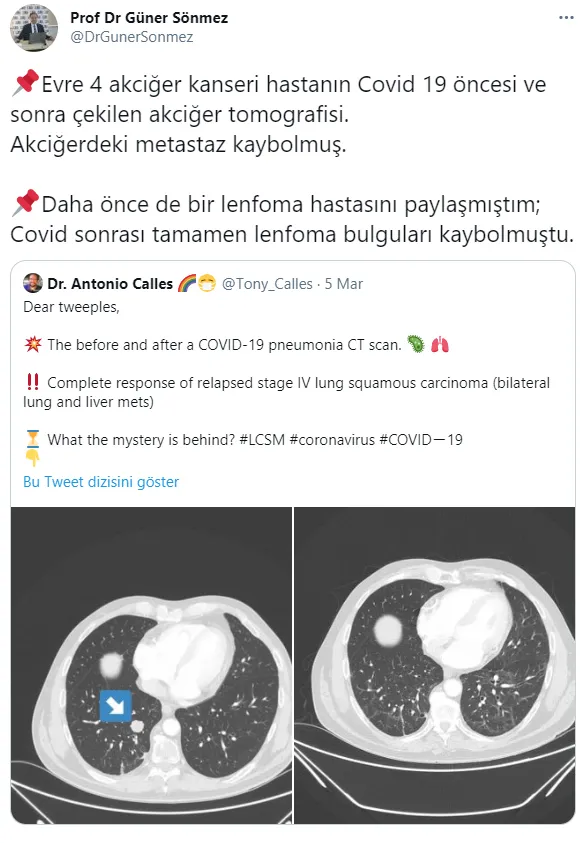

Prof. Dr. Güner Sönmez, "Evre 4 akciğer kanseri hastanın Covid 19 öncesi ve sonra çekilen akciğer tomografisi.

Akciğerdeki metastaz kaybolmuş. Daha önce de bir lenfoma hastasını paylaşmıştım; Covid sonrası tamamen lenfoma bulguları kaybolmuştu.

Muhtemelen Corona virüse karşı oluşan antikorlar ve hücresel bağışıklık, kanser hücrelerine de müdahale ediyor." ifadelerini kullandı.

Sönmez, "61 yaşında erkek hastaya lenf bezelerinin şişmesi üzerine biyopsi yapılıyor ve Hodgkin lenfoma (lenf kanseri) tanısı konuyor. Bu tanıdan hemen sonra da #COVID19 oluyor. Kanser tedavisi-kortizon verilmiyor. 4 ay sonra lenfomanın iyileştiği görülüyor. İlk çekilen PET/CT ve 4. ay" dedi.